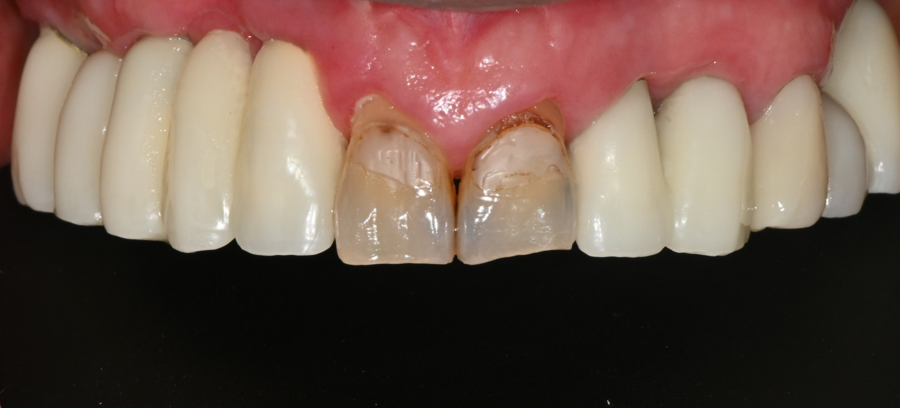

내원 당시 상태

환자분은 오랜 기간 사용한

오래된 앞니 보철물 때문에

색이 노랗게 변했고

치아 사이가 벌어져 보이고

웃을 때 앞니 모양이

마음에 들지 않는다고 호소하셨습니다.

또한 치아 표면이 많이 닳아 있어

‘사진 찍을 때 웃기 어렵다’고 하셨습니다.

앞니는 얼굴 인상을 결정하는 부위라

환자분의 고민이 충분히 이해되는 상황이었습니다.